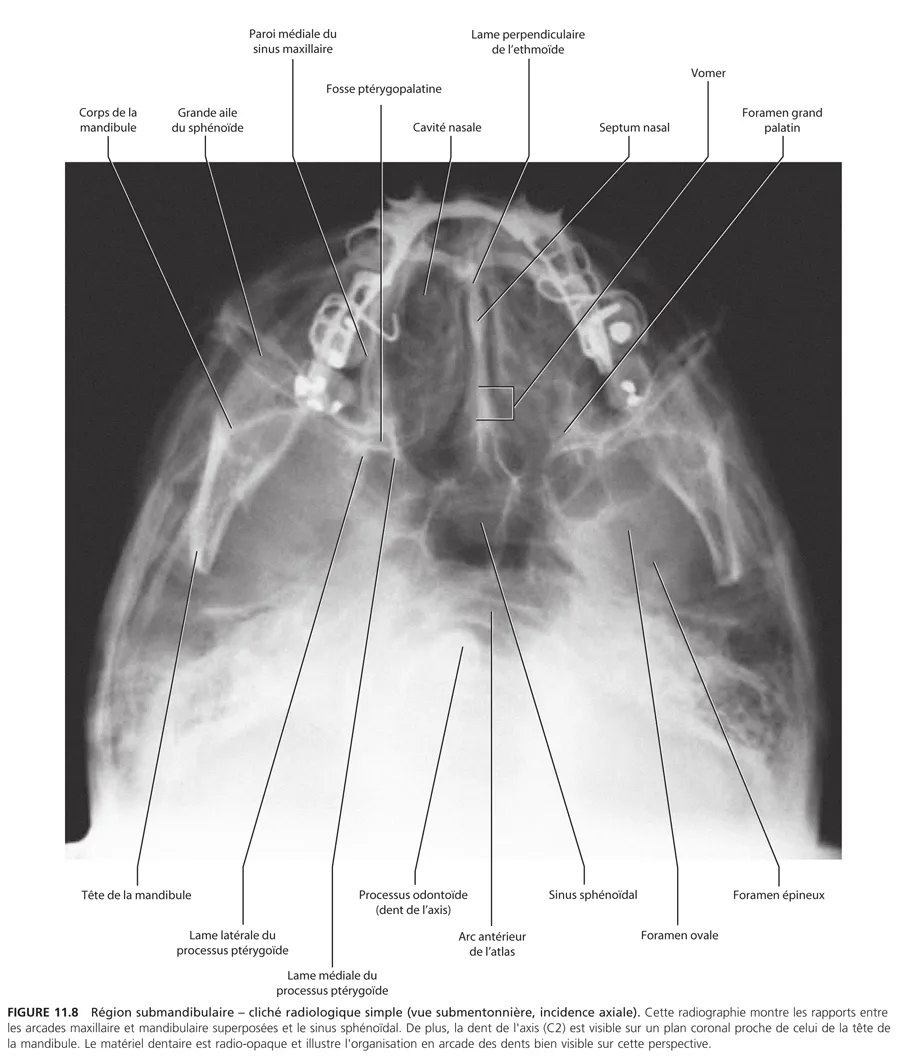

Fig11 8